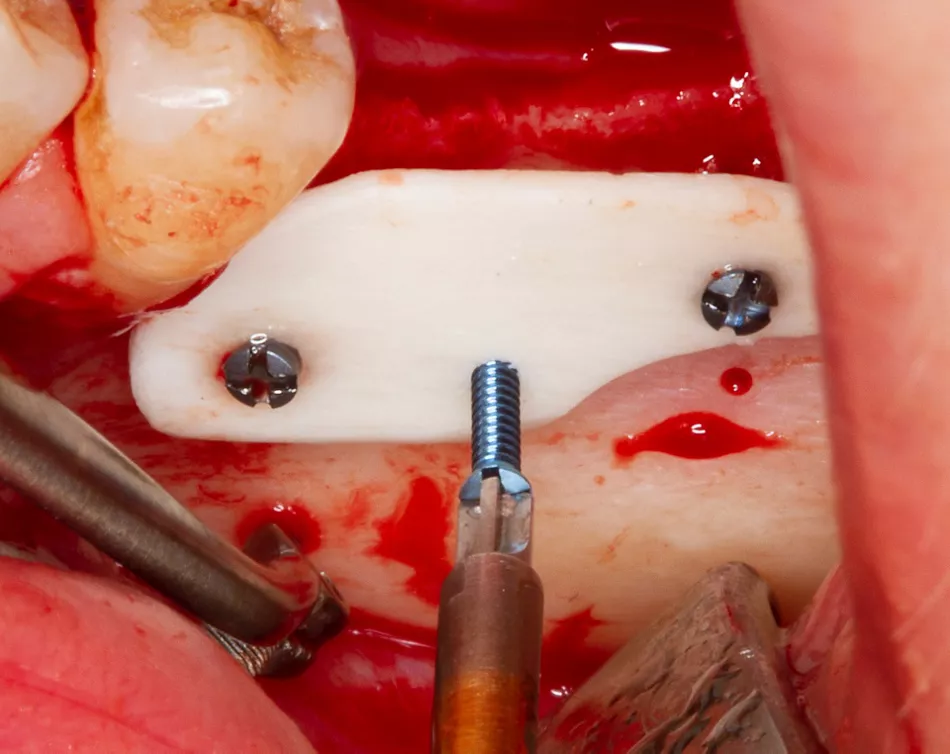

An allogeneic cortical plate (Botiss maxgraft® cortico, 25×10×1mm) was shaped and fixed with three Maxdrive screws (Figure 4).

Figure 4: Adaptation and fixation of the allogeneic shell plate

The space between the plate and native bone was filled apically with 0.5ml of Botiss maxgraft® granules (<2 mm particle size) and crestally with autologous bone chips (harvested using Safescraper® from the left retromolar area) (Figure 5).

Figure 5: Placement of graft material in two layers: allogeneic particles (<2mm size) in the “bottom” and autogenous bone chips “on the top”